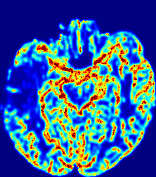

TimeSlice(i)(ii)(iii)(iv)(v)(vi)Refer to caption00777141414212121282828353535Refer to caption(a)(b)Refer to captionRefer to captionRefer to captionRefer to captionRefer to captionRefer to captionRefer to captionRefer to captionRefer to captionRefer to captionRefer to captionRefer to captionRefer to captionRefer to captionRefer to captionRefer to captionRefer to captionRefer to caption(a)(b)Refer to captionRefer to captionRefer to captionRefer to captionRefer to captionRefer to captionRefer to captionRefer to captionRefer to captionRefer to captionRefer to captionRefer to captionRefer to captionRefer to captionRefer to captionRefer to captionRefer to captionRefer to caption(a)(b)Refer to captionRefer to captionRefer to captionRefer to captionRefer to captionRefer to captionRefer to captionRefer to captionRefer to captionRefer to captionRefer to captionRefer to captionRefer to captionRefer to captionRefer to captionRefer to captionRefer to captionRefer to caption(a)(b)Refer to captionRefer to captionRefer to captionRefer to captionRefer to captionRefer to captionRefer to captionRefer to captionRefer to captionRefer to captionRefer to captionRefer to captionRefer to captionRefer to captionRefer to captionRefer to captionRefer to captionRefer to caption(a)(b)Refer to captionRefer to captionRefer to captionRefer to captionRefer to captionRefer to captionRefer to captionRefer to captionRefer to captionRefer to captionRefer to captionRefer to captionRefer to captionRefer to captionRefer to captionRefer to captionRefer to captionRefer to caption(a)(b)Refer to captionRefer to captionRefer to captionRefer to captionRefer to captionRefer to captionRefer to captionRefer to captionRefer to captionRefer to captionRefer to captionRefer to captionRefer to captionRefer to captionRefer to captionRefer to captionRefer to captionRefer to caption

Figure 5: Predicted concentration time series for the same patient shown in Fig. 3, where (i)-(vi) correspond to slices #1-6 respectively. Each grouped row displays (a) the measured concentration image sequences and (b) the predicted concentrations at corresponding time points.

3.2 Predicted CA Concentration

To better illustrate the prediction accuracy, and therefore the estimation accuracy of 𝐕𝐕{\bf V} and D𝐷{D}, of PIANO, we provide the corresponding predicted time-series of CA concentration images in Fig. 5 and Fig. 6 for the same patients in Fig. 3 and Fig. 4, respectively. We see that PIANO is capable of predicting the CA concentration given their initial state, indicating its ability to successfully capture 𝐕𝐕{\bf V} and D𝐷{D}. Note that although the concentration values for these two patients differ considerably, caused by the different total volume of injected CA, PIANO is still able to provide plausible estimates.